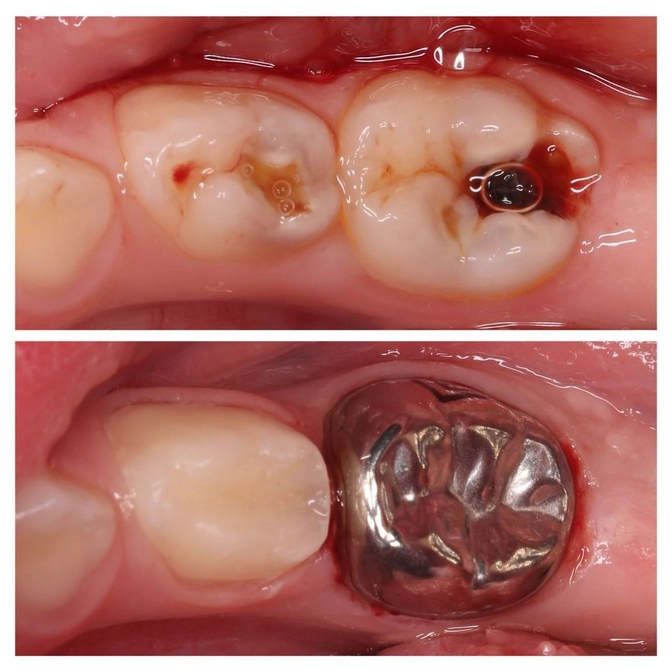

Ребенку на фото 4 года.

"Четверка" и "пятерка" уже сильно разрушены.

На обоих зубах пульпит.

• Пораженные ткани убраны;

• "Нерв" в этом случае удален частично;

• Внутрь зуба заложен биосовместимый материал;

• "Четверка" восстановлена композитным материалом;

• "Пятерку" закрыли металлической коронкой, т.к. большую пломбу ставить нецелесообразно из-за большой жевательной нагрузки.